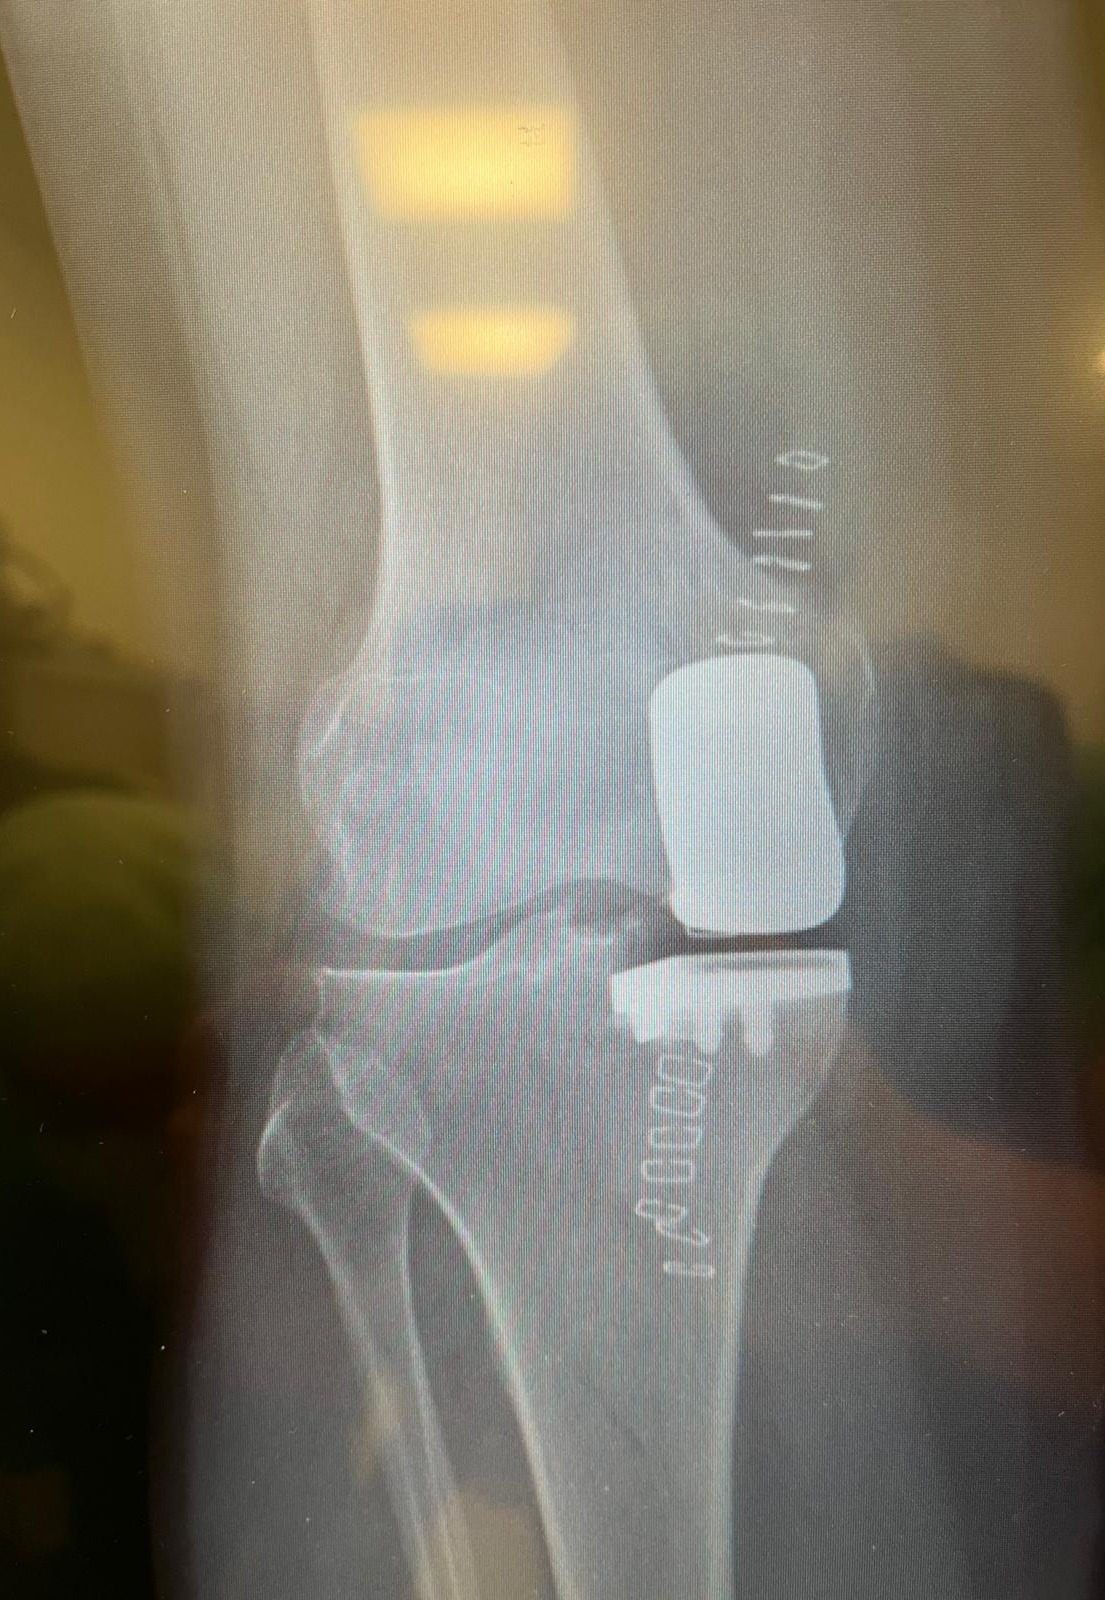

Radiografia Protesi Totale Ginocchio Allineamento Cinematico Radiografia Protesi Monocompartimentale

Chirurgia del Ginocchio

Dall'Artroscopia alle protesi personalizzate, scegliamo sempre il percorso meno invasivo per la tua articolazione, dalla medicina rigenerativa all'Allineamento Cinematico e protesi Monocompartimentali.